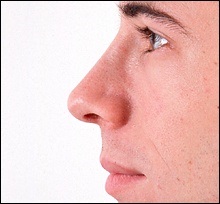

A fénykép a bal oldalon mutatja egy ember tipikus megnövekedett nazális gerinc. Ez jelentősen növeli az orrát előre. A fénykép után a művelet ugyanaz az ember nagyon jól néz ki.

A férfi látható a felső képen látható jól látható összes következményét a hosszúkás elülső orr-gerinc: határozottan kiálló orr, „kapcsolt” a felső ajak és columella túl nyitott. Azonban meg kell jegyezni, hogy az oka ezeket a „következmények” nem csak vetített előre az orr gerinc.